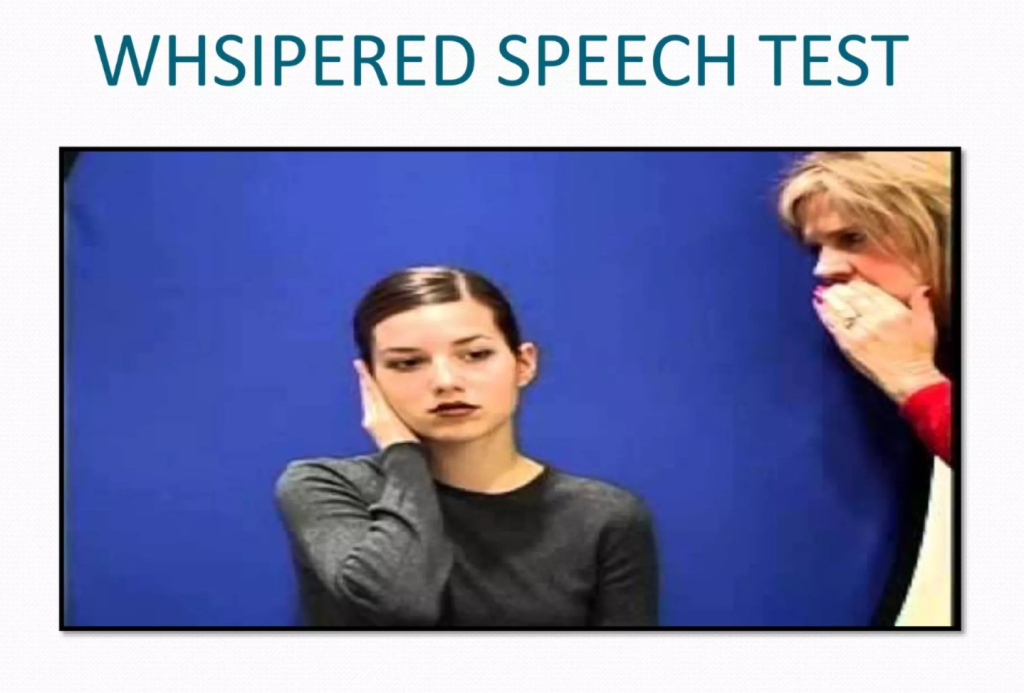

♦ whispered speech test (વિસ્પરડ સ્પીચ ટેસ્ટ)

- આ વિસ્પરડ સ્પીચ ટેસ્ટ (whispered speech test)માં કોઈપણ હેલ્થ પ્રોફેશનલ એ પેશન્ટ ને તેનો એક કાન એ એક હાથ ના આંગળીઓ વડે કવર કરવા કહે છે .અને કોઈપણ હેલ્થ પ્રોફેશનલ એ એક ફૂટ અથવા બે ફૂટ તેની પાછળ ઉભે છે .અને અમુક શબ્દોની સિરીઝ બોલે છે તેમણ આ શબ્દો રીપીટ કરવાના હોય છે જો તેણ ન સાંભળ્યા હોય તો હેલ્થ પ્રોફેશનલ એ મોટા અવાજે આ શબ્દો બોલે છે જ્યાં સુધી તે ન સાંભળી શકે ત્યાં સુધી હેલ્થ પ્રોફેશનલ એ શબ્દોની સિરીઝ બોલે છે અને એ એક કાન અને બીજા કાનમાં Hearing અલગ અલગ ચેક કરવામાં આવે છે.